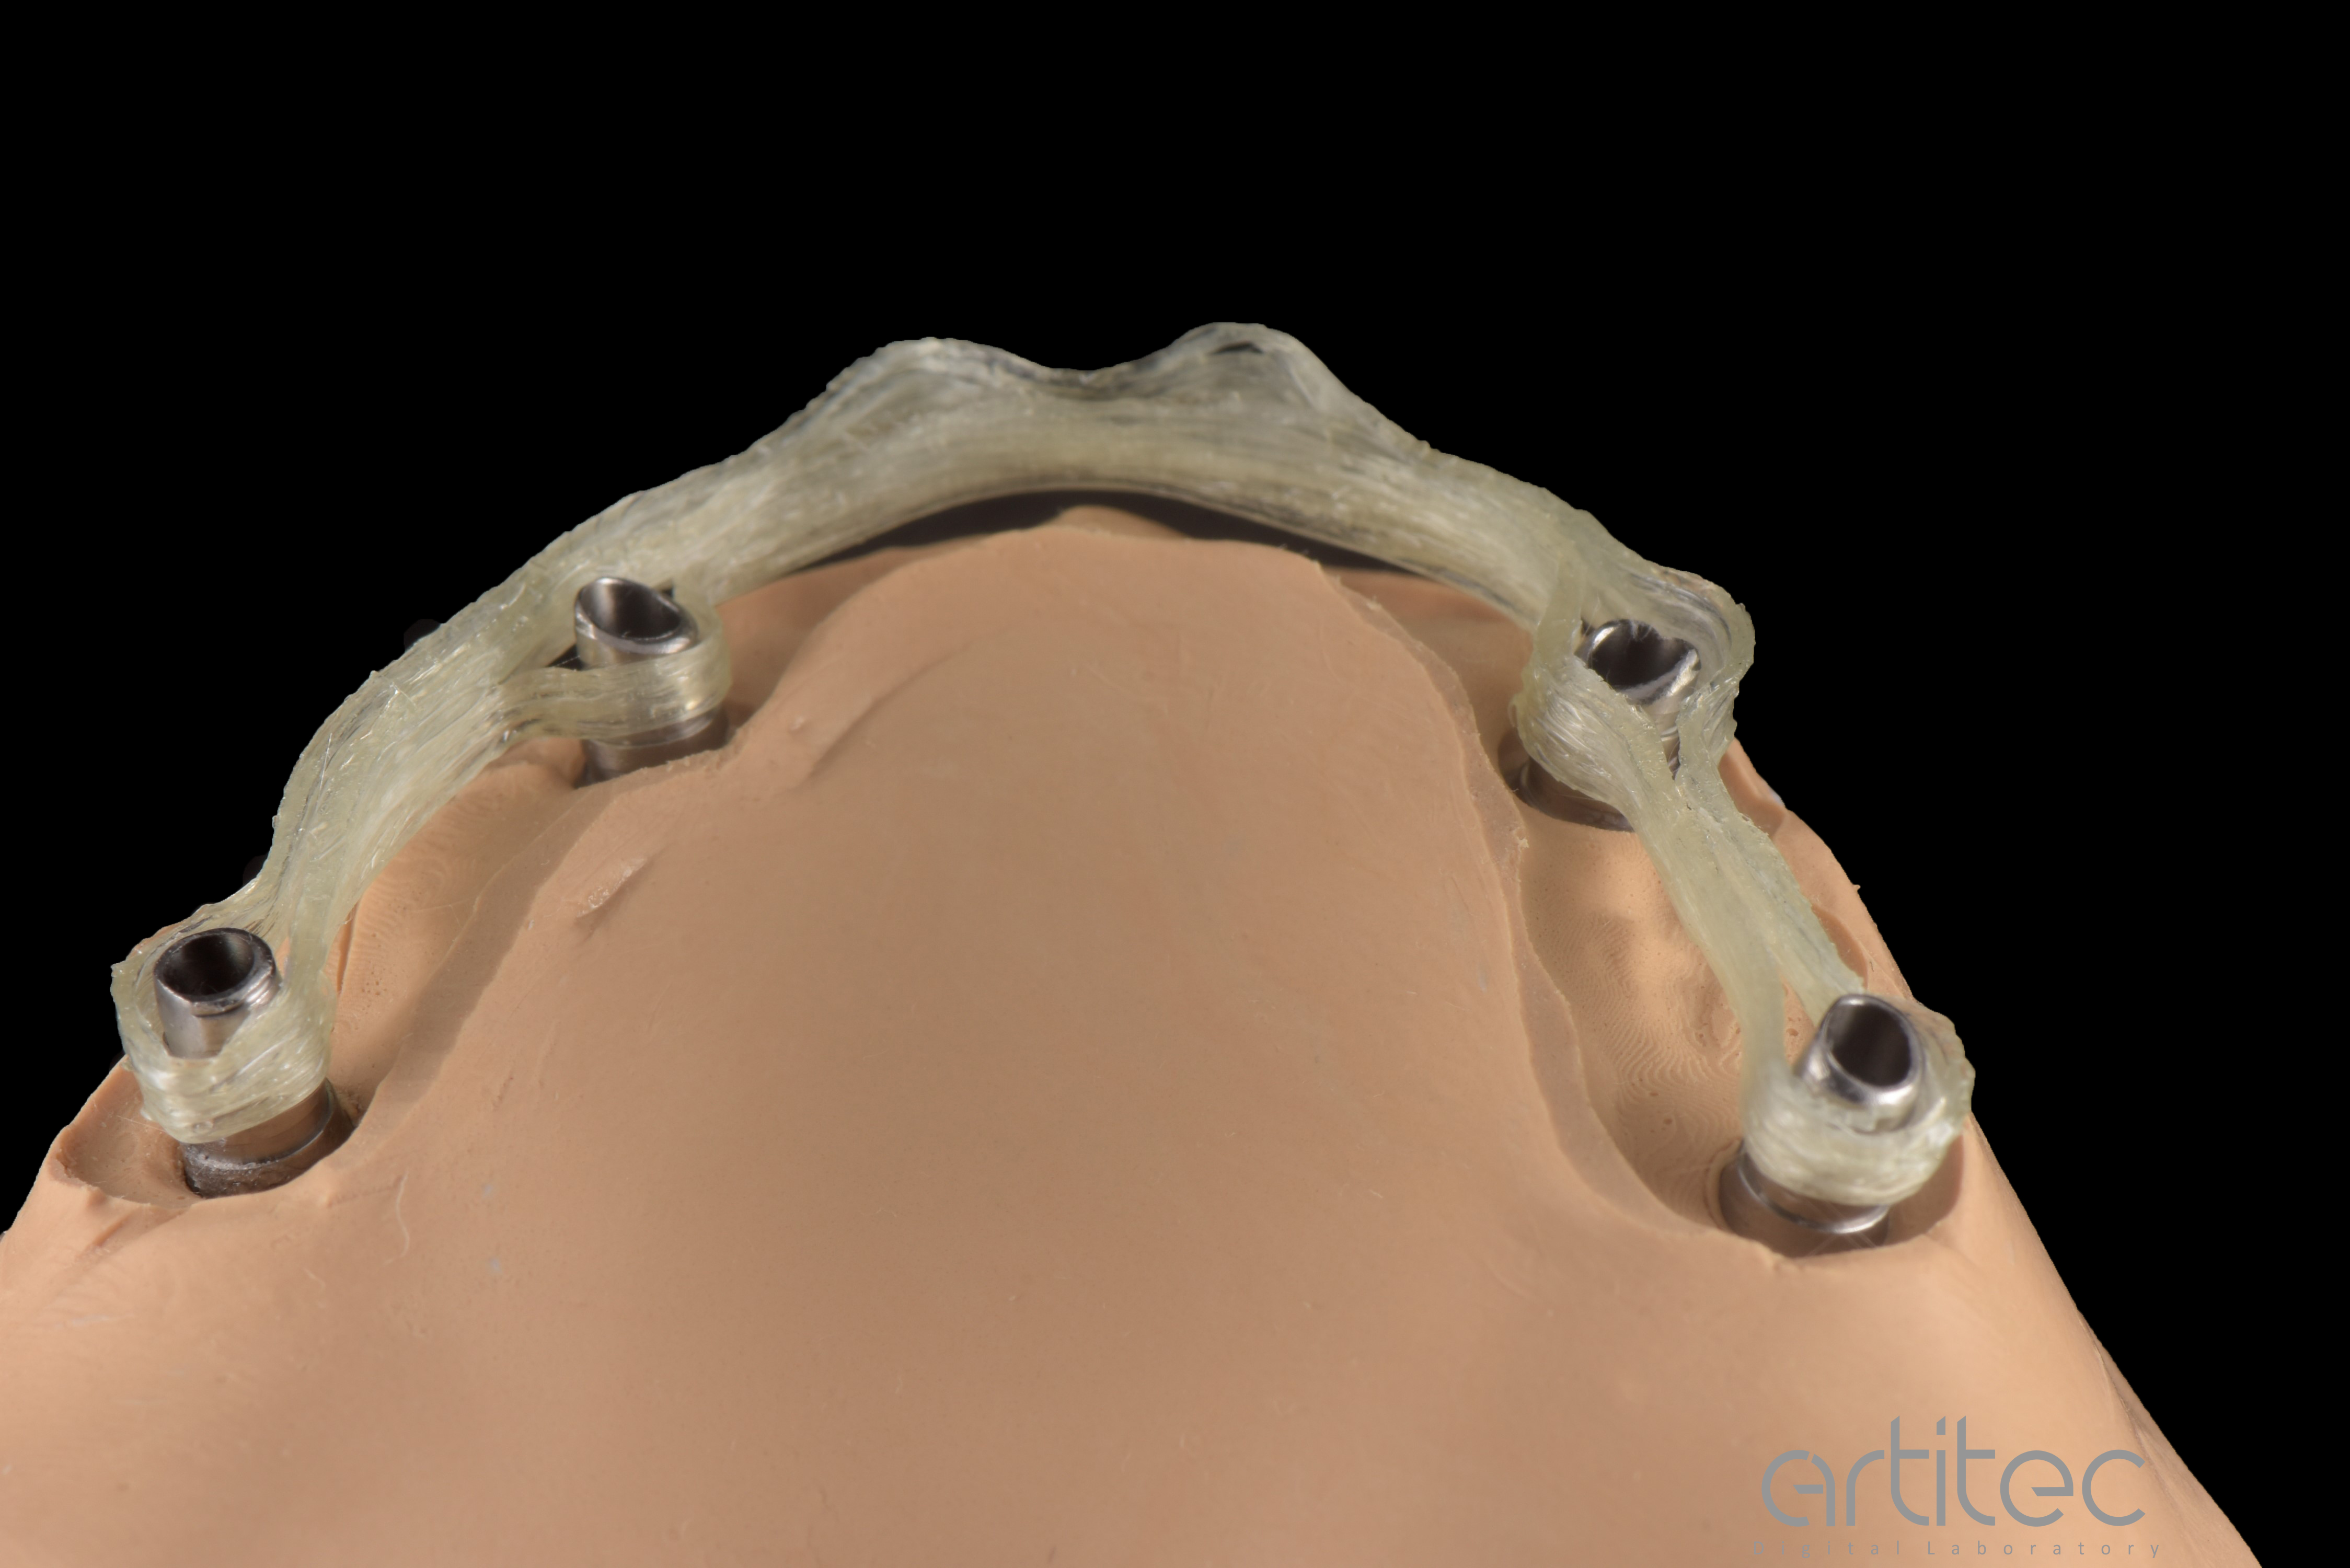

Fig. 21 Vista basale con inserimento dei linker

Fig. 22 Controllo e test di avvitamento su modello ibrido

Fig. 26 Barra Hi-Fiber posizionata sui linker